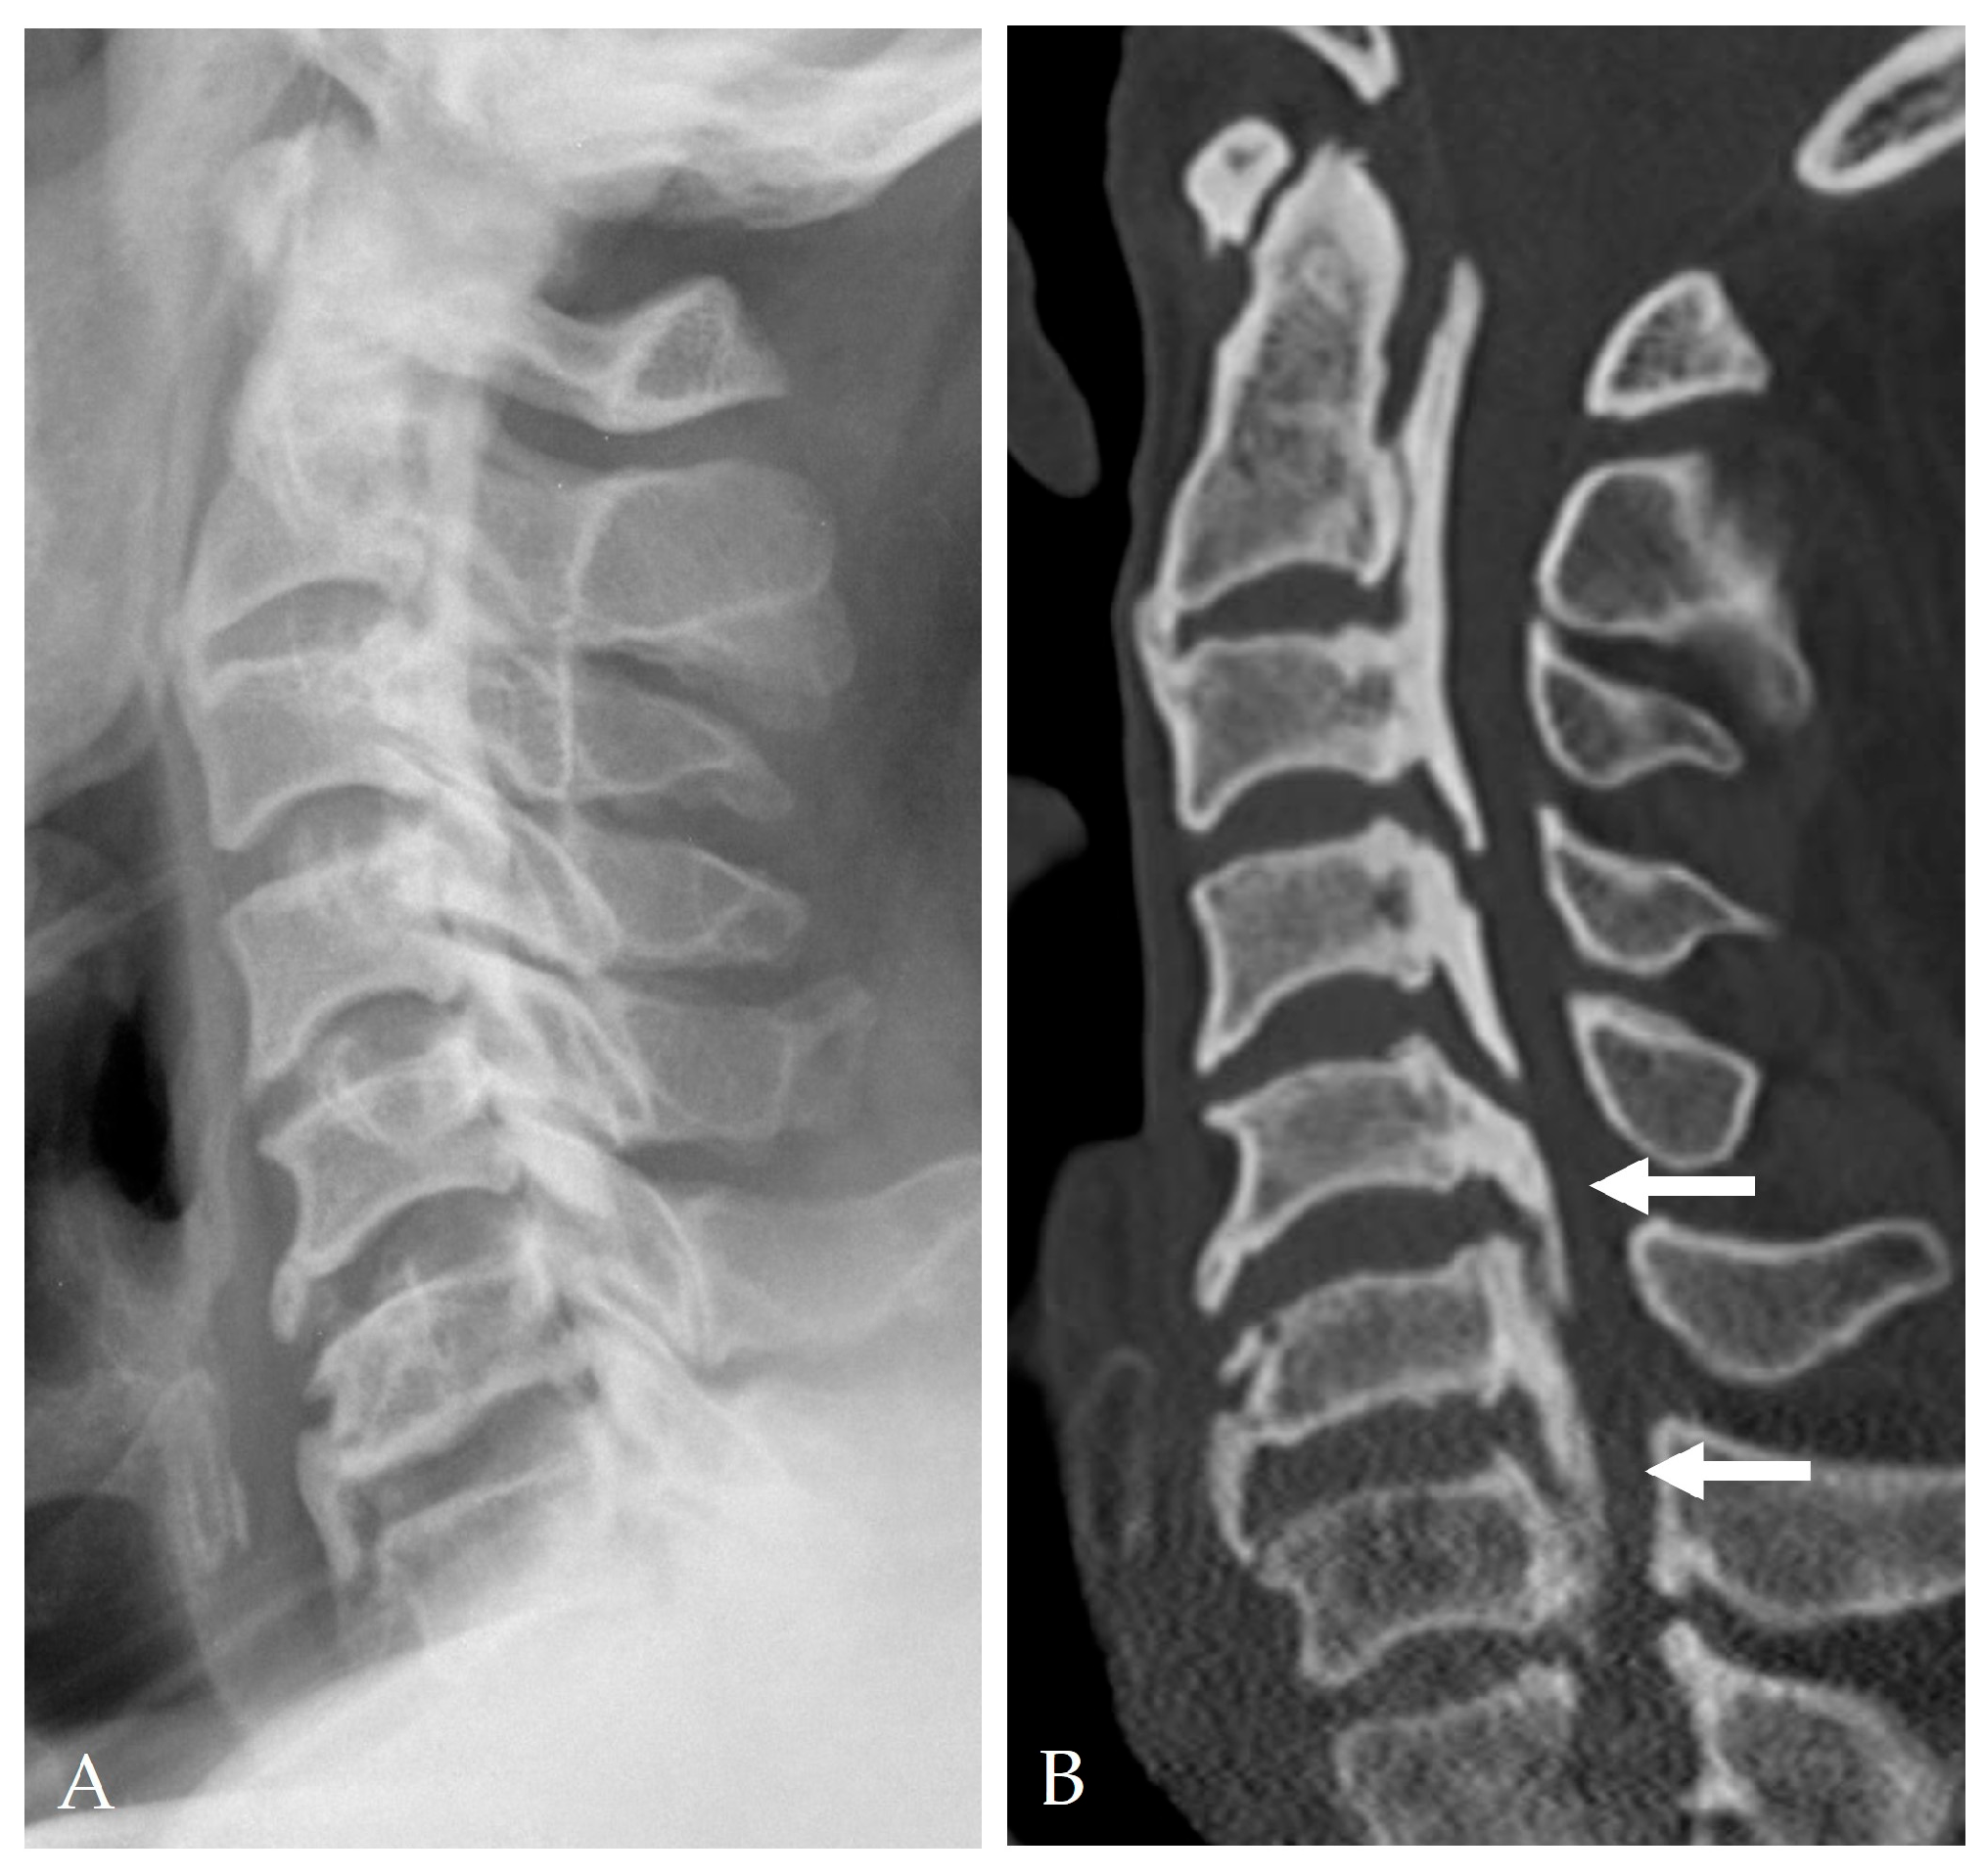

2.4. Radiologic Predictors and Morphological Correlates

- Fujiyoshi, T.; Yamazaki, M.; Kawabe, J.; Endo, T.; Furuya, T.; Koda, M.; Okawa, A.; Takahashi, K.; Konishi, H. A new concept for making decisions regarding the surgical approach for cervical ossification of the posterior longitudinal ligament: The K-line. Spine 2008, 33, E990–E993. [Google Scholar] [CrossRef]

- Min, J.H.; Jang, J.S.; Lee, S.H. Clinical significance of the double-layer sign on computed tomography in OPLL. Neurosurgery 2007, 61, 118–121. [Google Scholar] [CrossRef]

- Yang, H.; Yang, L.; Chen, D.; Wang, X.; Lu, X.; Yuan, W. Implications of different patterns of the “double-layer sign” in cervical OPLL. Eur. Spine J. 2015, 24, 1631–1639. [Google Scholar] [CrossRef]

- Epstein, N.E. Identification of OPLL extending through the dura on preoperative CT of the cervical spine. Spine 2002, 27, 182–186. [Google Scholar]

- Mizuno, J. Radiologic evaluation of ossification of the posterior longitudinal ligament with dural ossification. Neurosurg. Clin. N. Am. 2018, 29, 55–61. [Google Scholar] [CrossRef] [PubMed]

| Radiological Predictors | Double-layer and hook signs, K-line negativity, OPLL occupying ratio ≥ 60% |